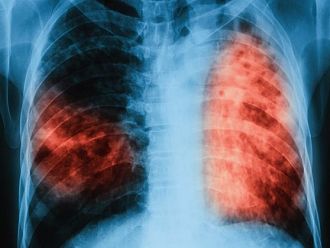

От утре, 11-ти декември, започва седмица на отворените врати, посветена на туберкулозата. В периода 11-15 декември ще се проведат безплатни прегледи за туберкулоза в лечебни заведения за диагностика и лечение на туберкулоза във всички областни градове на страната, съобщават от МЗ.

По време на „Седмицата на отворените врати” на всеки желаещ се предлага скрининг за риска от туберкулоза чрез анкета и консултации. При откриването на случаи на туберкулоза своевременно се предприемат мерки за хоспитализация и лечение, в резултат на което се прекъсва веригата за предаване на инфекцията.

По време на третата кампания за 2017 г., която се проведе през месец септември, анкетирани за туберкулоза са 3079 лица, от тях в риск от туберкулоза - 1738, на които са извършени медицински прегледи и допълнителни изследвания. Открити са 34 лица с туберкулоза и 72 лица с латентна туберкулозна инфекция. На всички се прилага безплатно лечение и химиопрофилактика. Най-много лица са преминали в МБАЛ „Св. Георги" - Пловдив, СБАЛПФЗ - Бургас, СБАЛПФЗ - Пазарджик, МБАЛ „Д-р Иван Селимински" - Сливен, МБАЛ - Силистра и СБАЛПФЗ - Враца.

От началото на 2017 г. общо анкетирани за туберкулоза са 9574 лица, на 5873 лица в риск за туберкулоза са извършени медицински прегледи и допълнителни изследвания. Открити са 97 лица с туберкулоза, които са започнали лечение, и 445 лица с латентна туберкулозна инфекция, които провеждат химиопрофилактика.

По време на проведените за периода 2009 г. – септември 2017 г. „Седмици на отворени врати” анкетираните за туберкулоза 99 691 лица. Броят на лицата, диагностицирани с туберкулоза и насочени за лечени, е 1099. Други 3906 души са открити с латентна туберкулозна инфекция и са обхванати с химиопрофилактика.